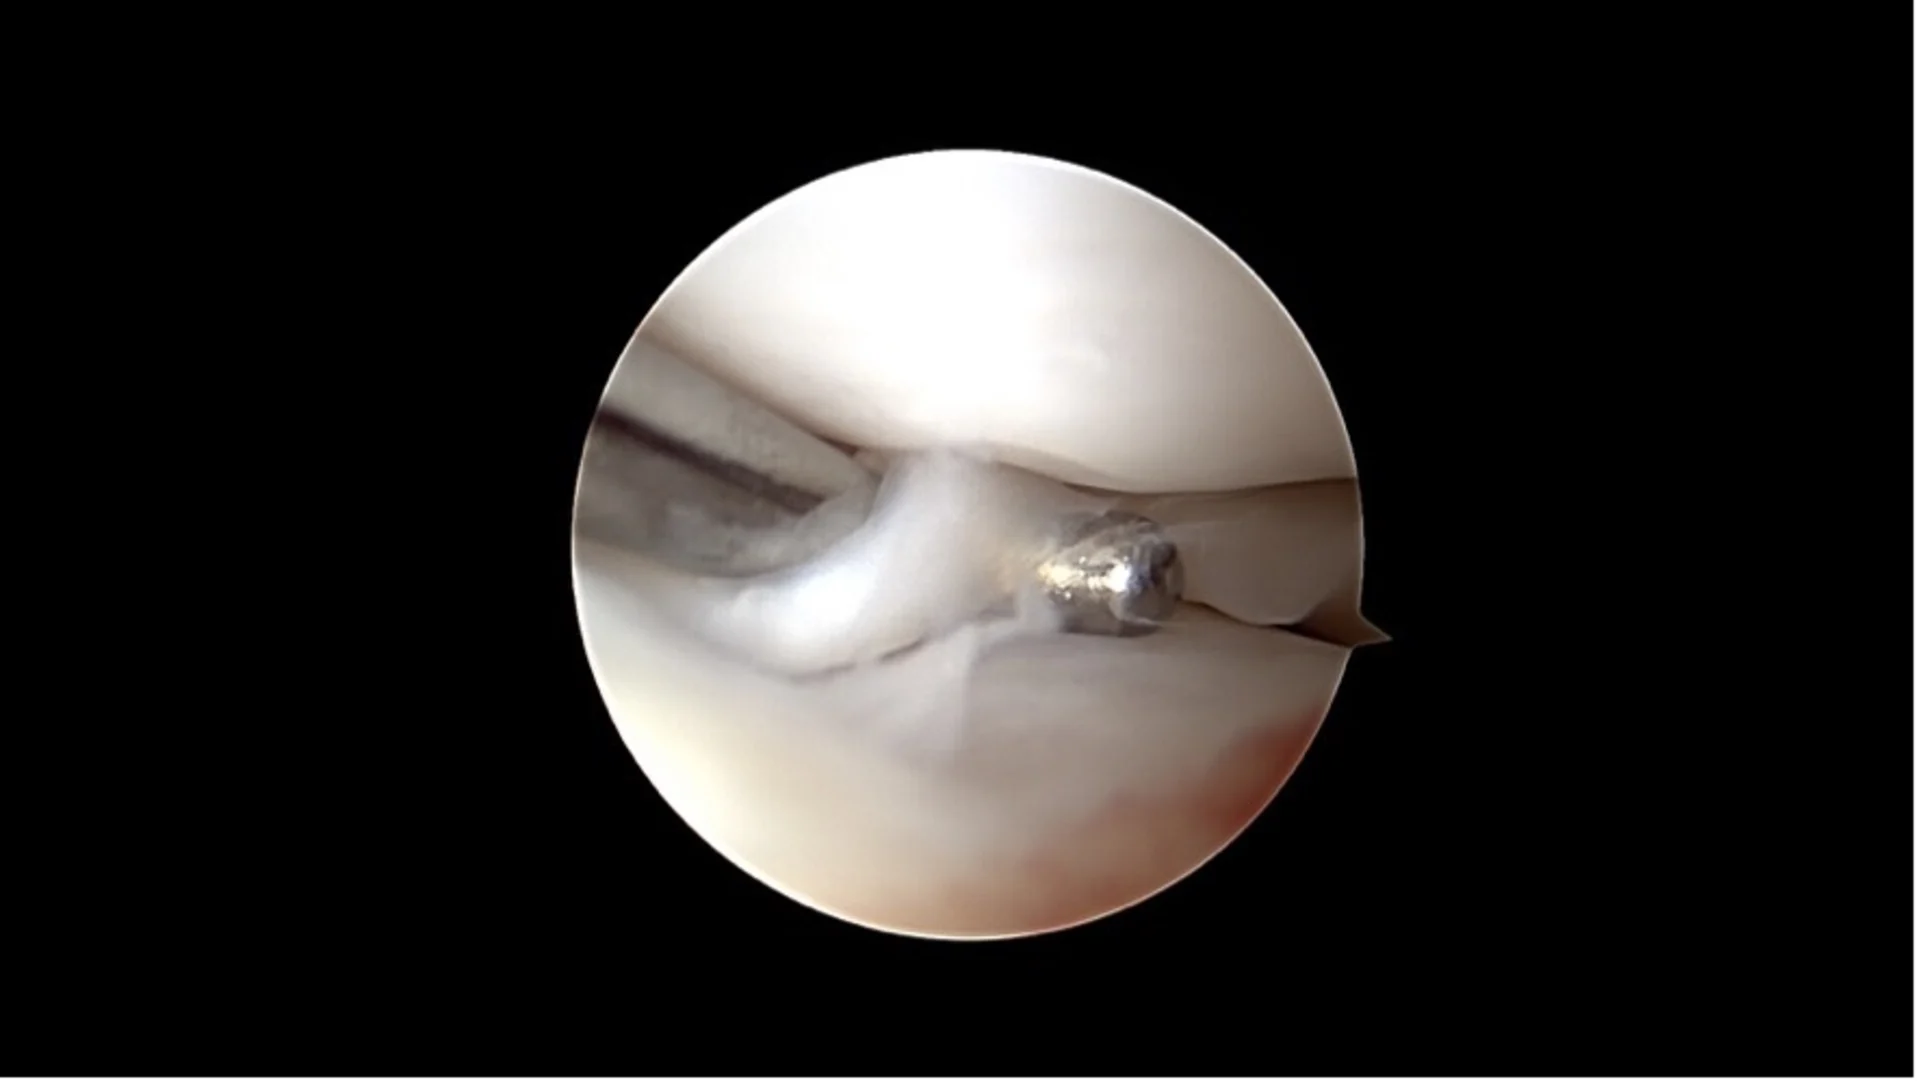

Ein beginnender Kreuzbandriss versteckt sich unter dem auf dem ersten Blick unauffälligen restlichen Kreuzband

Ein kompletter Kreuzbandriss

Arthroskopie: Diese Technik ermöglicht eine direkte Sicht auf das Gelenkinnere mit Hilfe einer kleinen Kamera. Über nur wenige Millimeter grosse Hautöffnungen lassen sich Veränderungen am Kreuzband sowie begleitende Schäden wie Meniskusrisse erkennen und in vielen Fällen auch direkt behandeln.

Korbhenkel-artiger Meniskus Riss